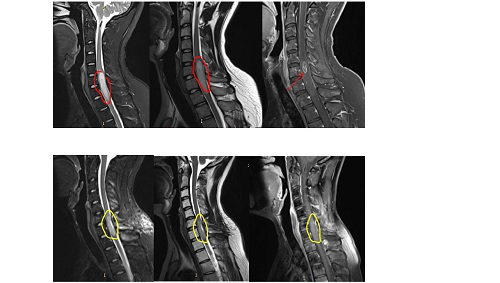

选择微创方法(半椎板切除术),伴随术中超声检查,术中神经生理学监测和细致的显微外科技术,较大切除肿瘤的同时尽可能避免损伤脊柱功能和结构,术后疼痛较轻,患者可尽早进行康复训练,住院时间较短,术后脊柱不稳定性较椎板切除术减少。如今,半椎板切除术已广泛用于切除各种脊髓病变,包括髓内海绵状血管瘤。

(A-C)3D-CT扫描显示位于C1-2水平的髓内CM的术后图像。(B)在术中脊髓表面观察到含铁血黄素染色。(C)完全切除髓内CM,显示髓鞘切开的程度。